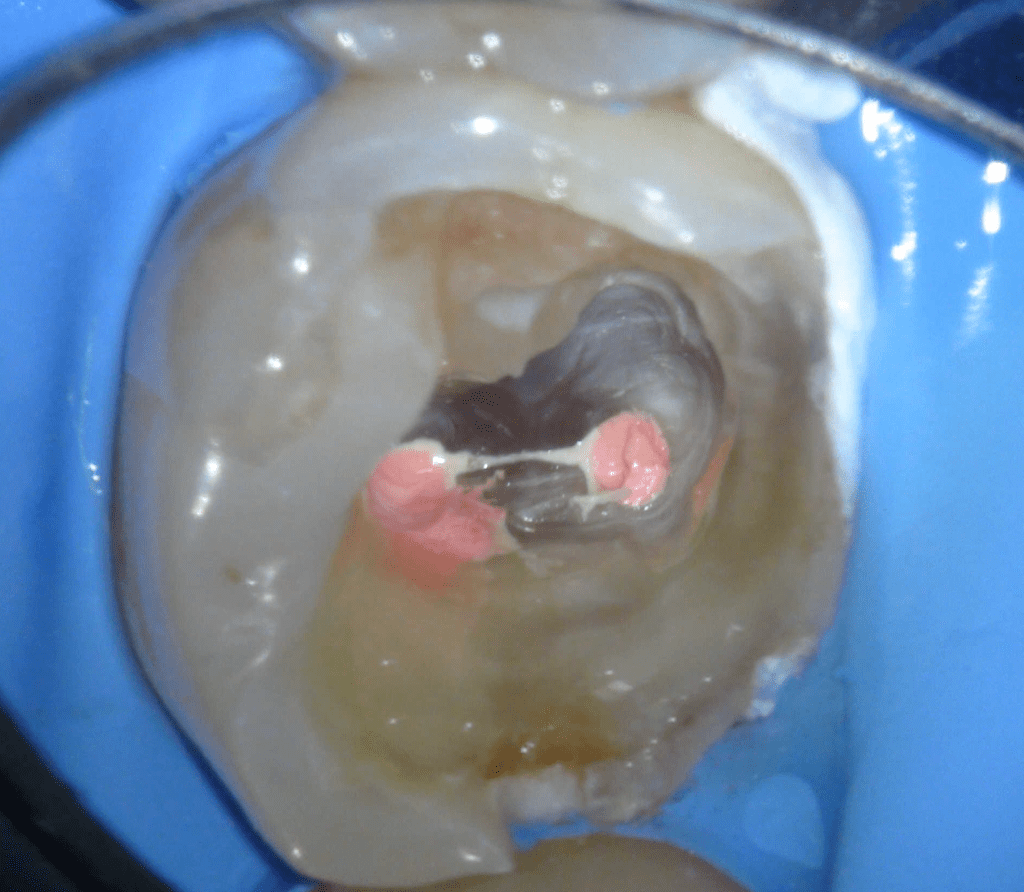

Pulpotomía biodentine + reco preendio